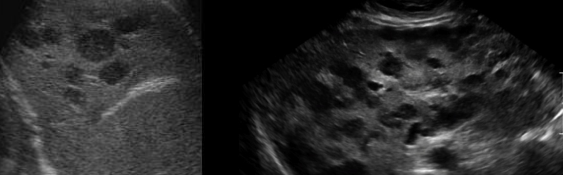

hepatic candidiasis

(most commonly) pneumocystis carinii (associated with hepatic granuloma)

hepatic granulomas (associated with pneumocystis carinii)